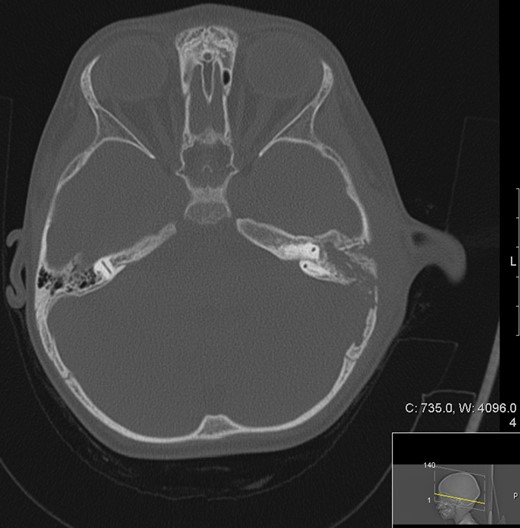

A CT scan of the patient at this point showed mastoiditis, a subperiosteal abscess and extradural abscess with extensive bony defects (Figs 1 and 2). The patient was initially started on IV ceftriaxone and metronidazole. Upon discussion with ENT specialists he underwent a left sided mastoid exploration and drainage of the extradural and peri sigmoid sinus collection on Day 2 of his admission. Surgical exploration found a large parietal subperiosteal abscess with bony defects and granulation tissue connecting with an extradural abscess. Histological diagnosis showed evidence of granulomatous osteomyelitis due to necrotizing granulomatous inflammation. Initial Zeihl-Neelson and Wade Fire stains for acid fast bacilli in tissue culture were negative.

Transverse computed tomography (bone window) image showing a left sided mastoiditis (white asterisk) bone extensive cortical bony destruction involving left petrous, squamous and mastoid bone as well as the adjacent parietal bone.